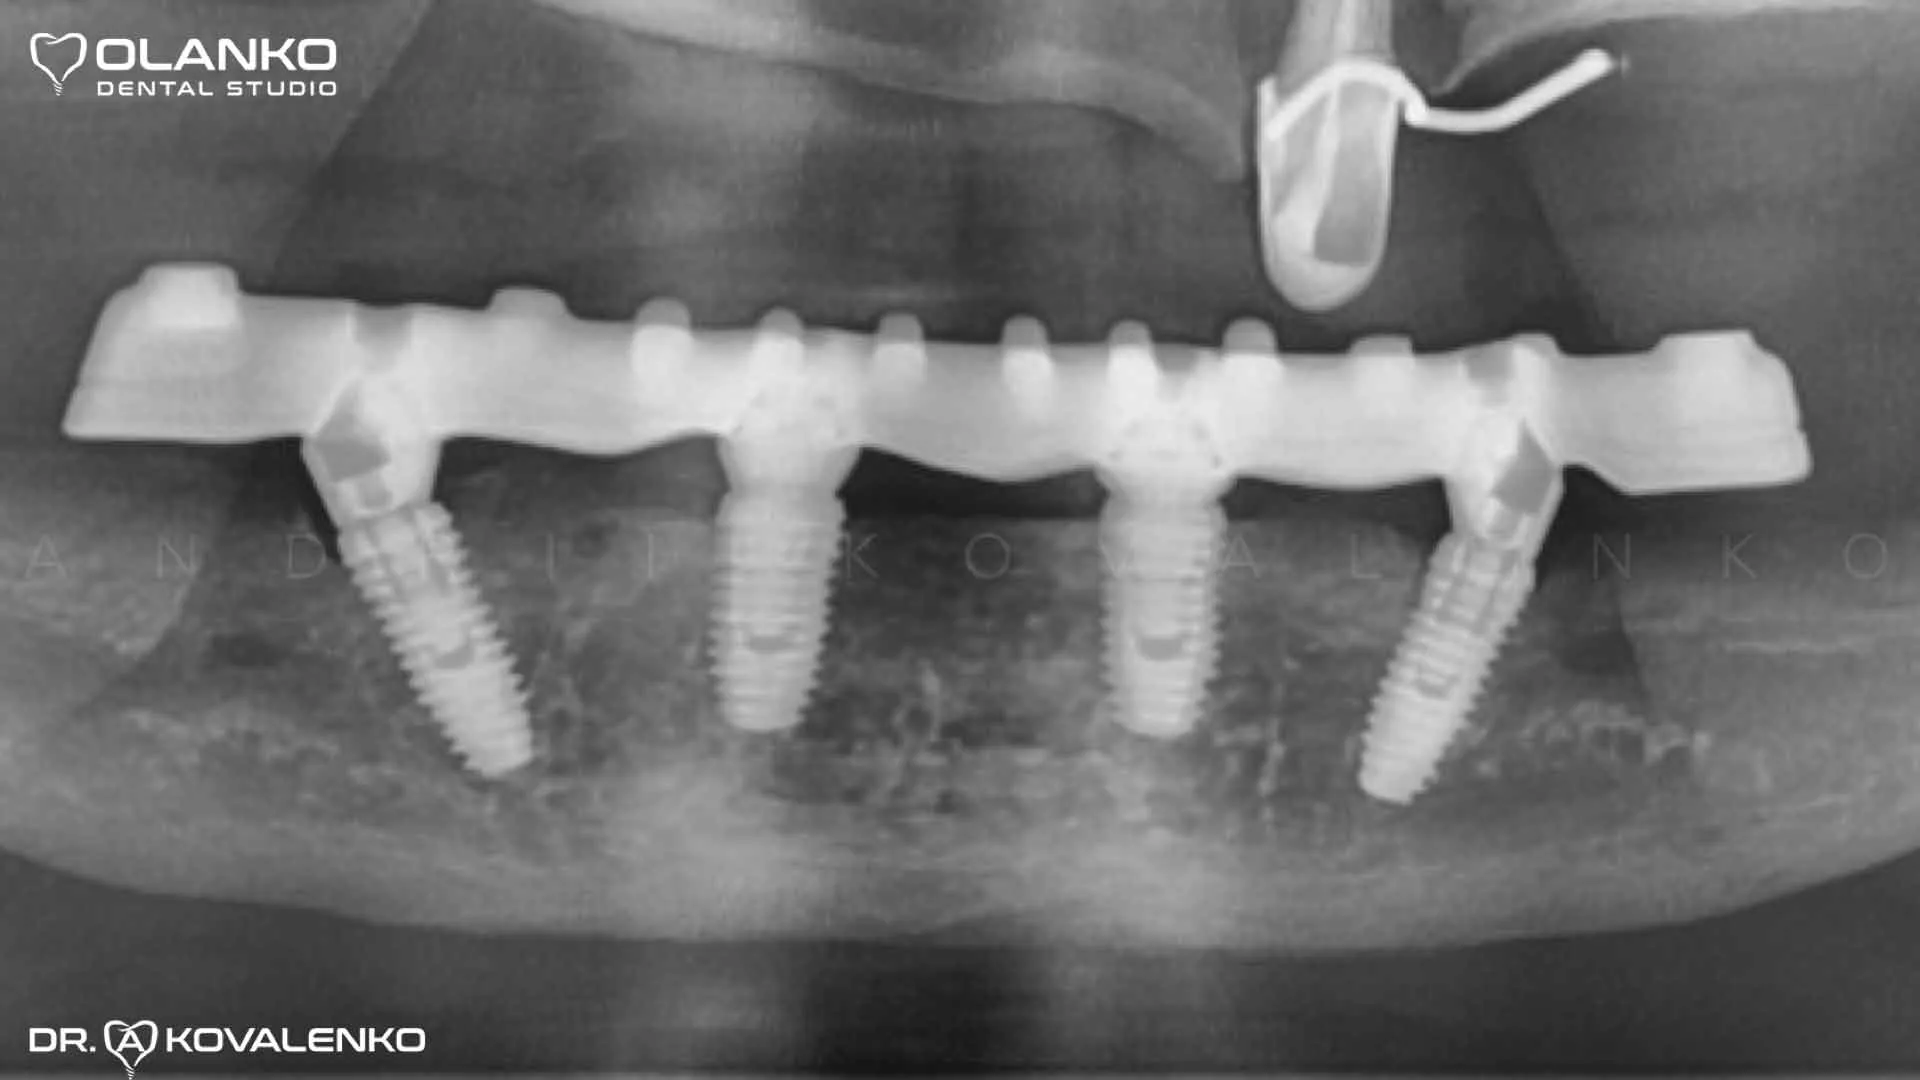

Пример протезирования по технологии All on 4 на беззубой нижней челюсти

Ситуация до установки имплантатов

Импланты Nobel система номер 1 в мире

Фото после установки и приживления имплантов

Фото после установки зубного протеза с опрой на 4 имплантата